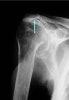

Cuff arthropathy

1. Sclerosis, atrophy, or irregularity of greater tuberosity

2. Notching between greater tuberosity and articular surface

3. Acromio-humeral distance < 6mm

4. Lateral new bone formation, erosion, and sclerosis of the undersurface of the acromion